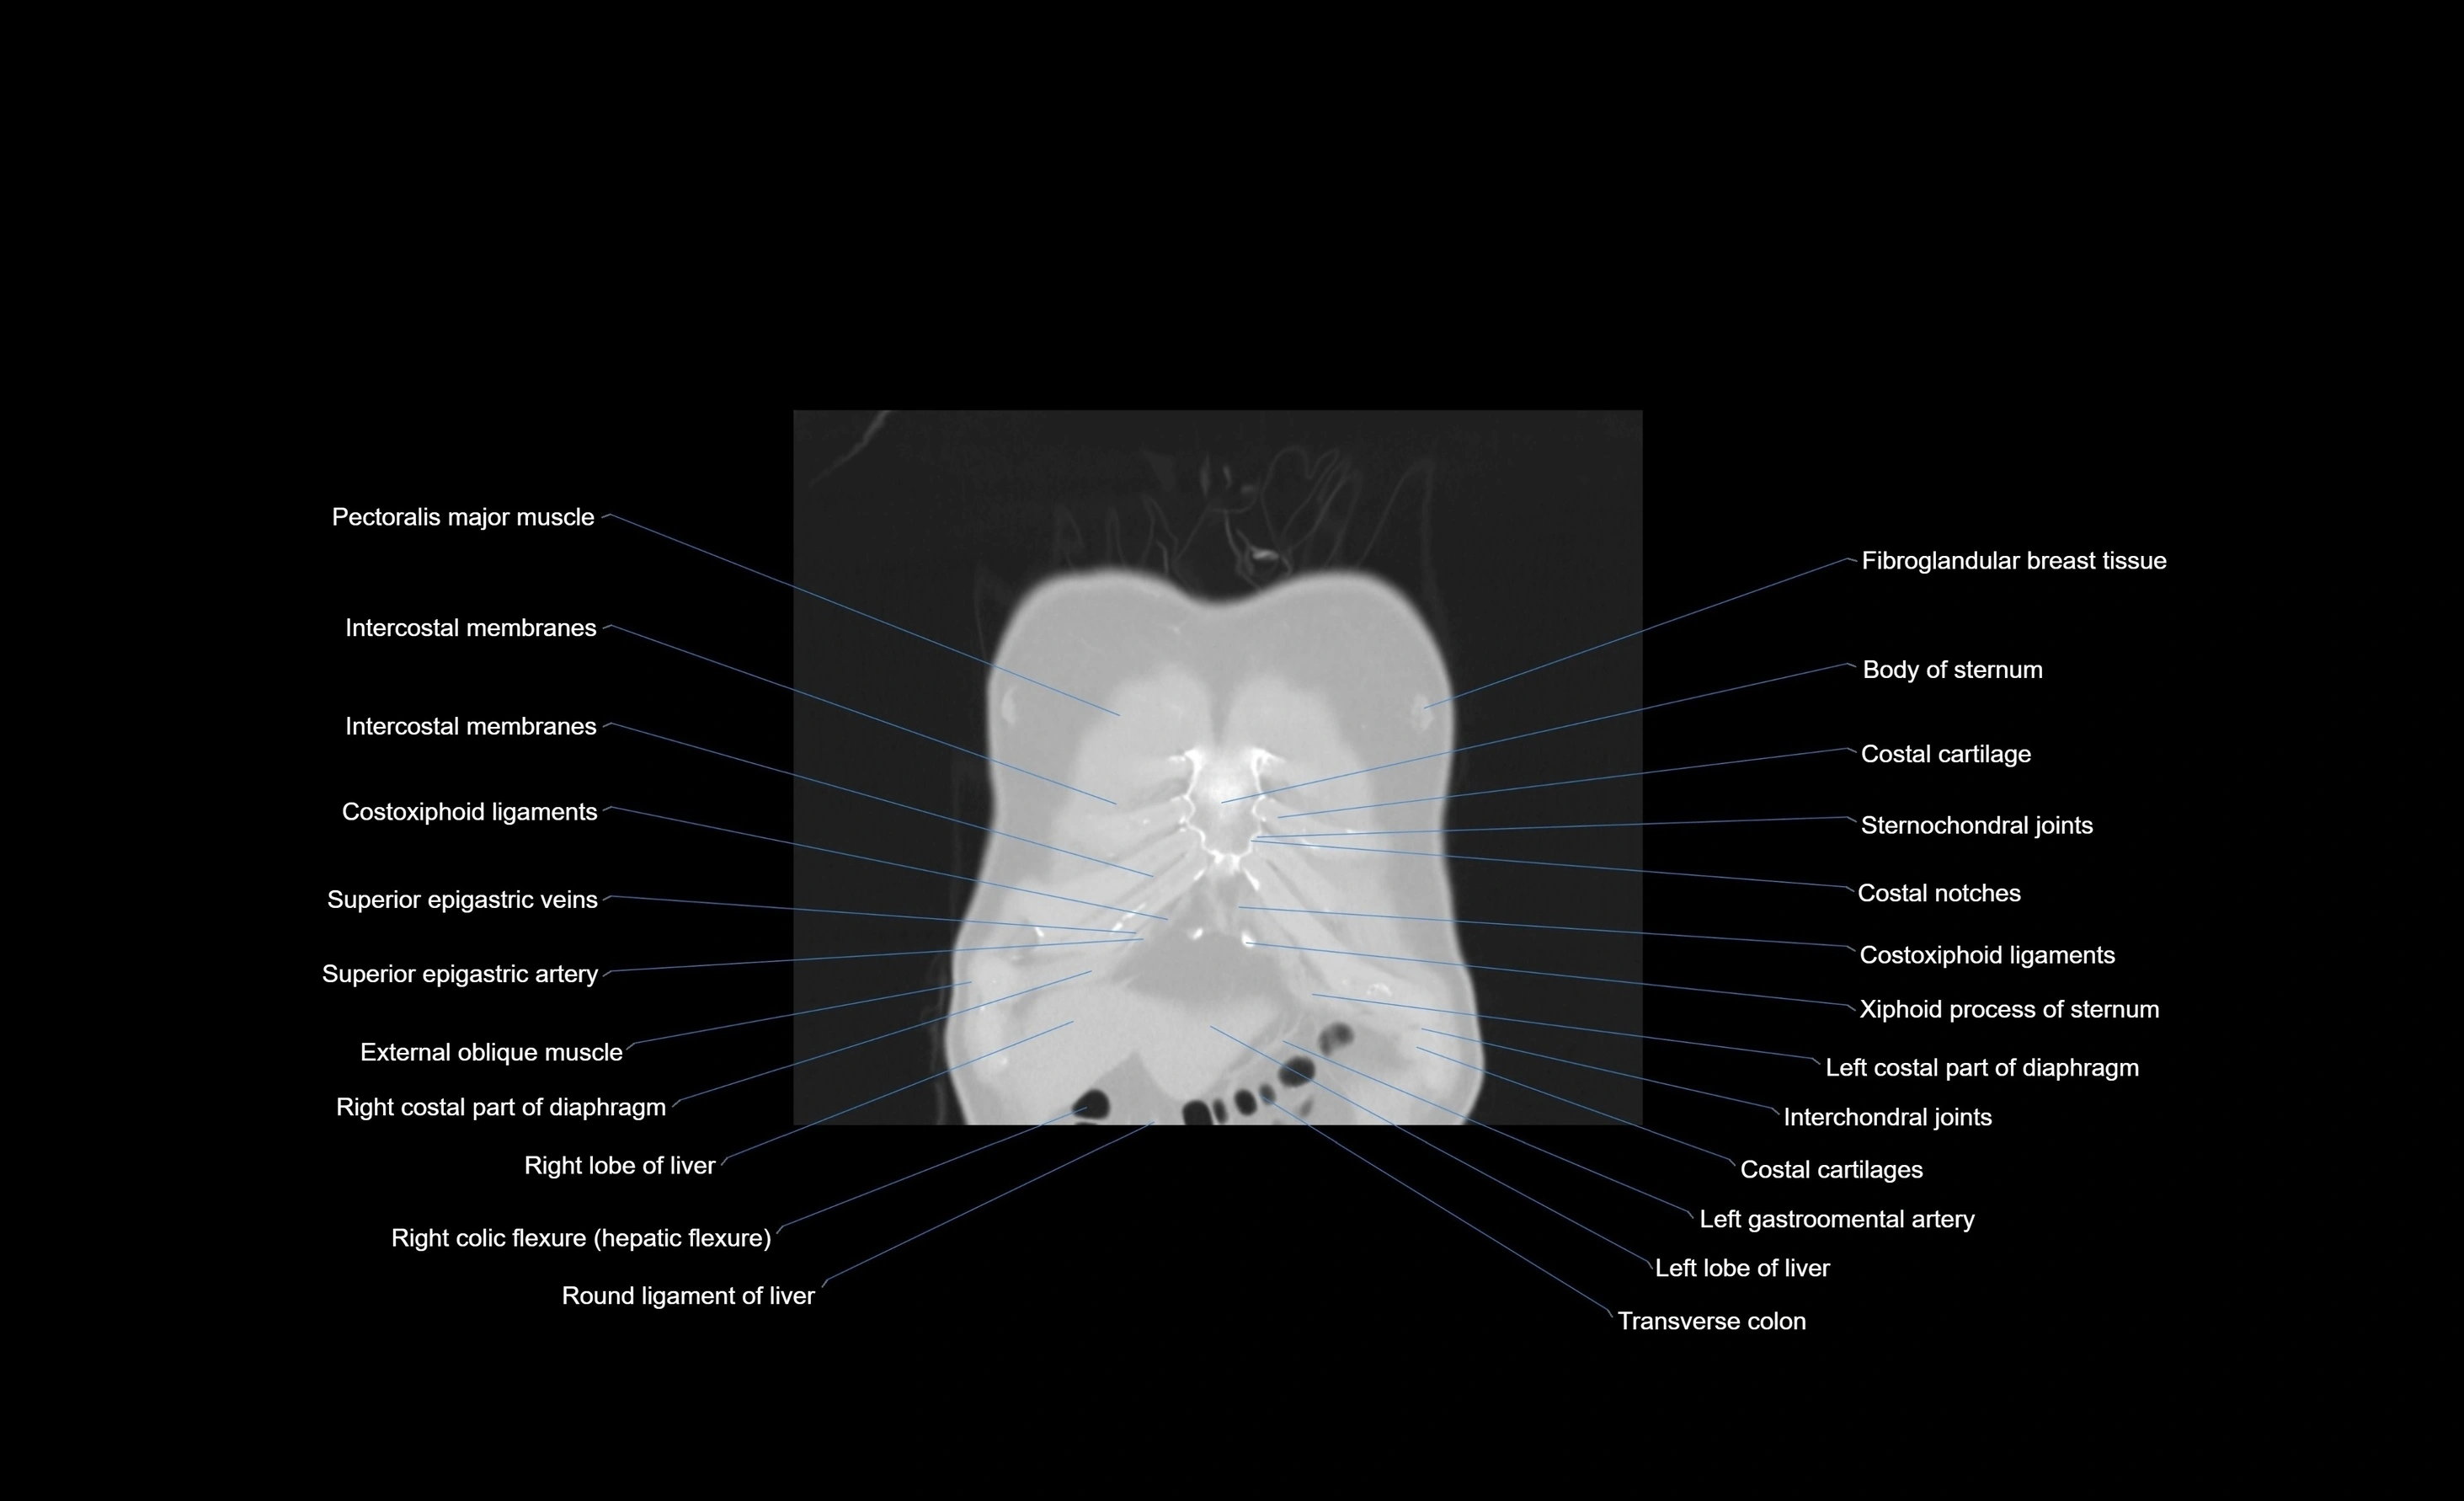

- Pectoralis major muscle

- Costoxiphoid ligaments

- Superior epigastric veins

- Superior epigastric artery

- External oblique muscle

- Costal cartilages

- Costal notches

- Left lobe of liver

- Right lobe of liver